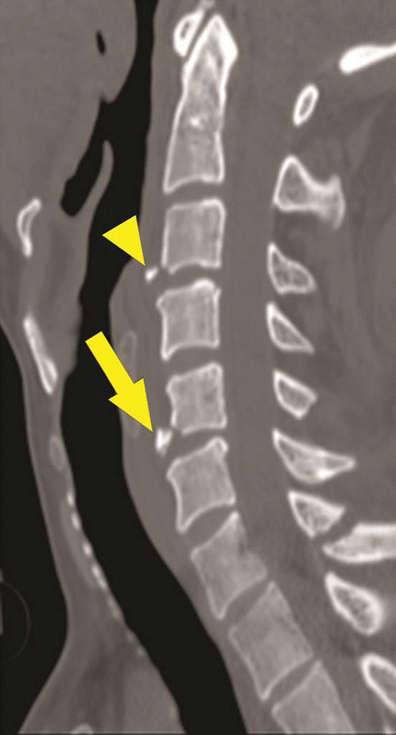

Hyperextension teardrop. Sagittal CT image shows small triangular avulsion fractures at the anteroinferior end plate of C3 (arrowhead) and C5 (arrow) without significant prevertebral soft tissue lesion. The triangular fragment at C5 is taller than wider, suggestive of hyperextension teardrop than hyperextension dislocation

Avulsion fracture in hyperextension dislocation. Sagittal CT image shows an avulsion fracture at the anterosuperior end plate of C7 (white arrow), with the transverse diameter wider than the vertical diameter. Avulsion of the posteroinferior corner of the C6 vertebral body is also seen (black arrow), which suggests avulsion of the posterior annulus or PLL